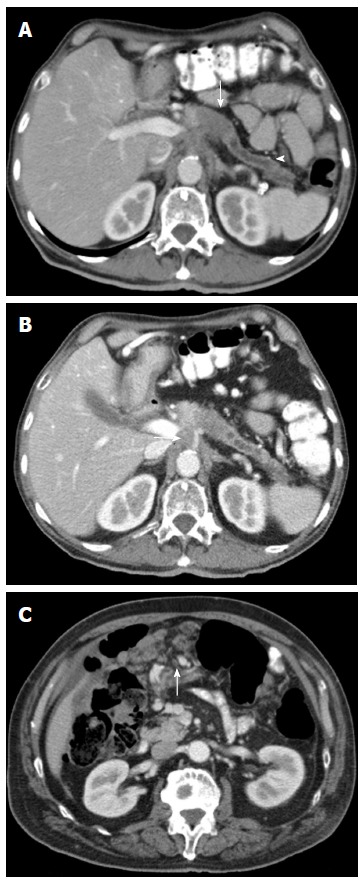

Bilgisayarlı tomografi ve manyetik rezonans görüntüleme yöntemleri pankreasın değerlendirilmesi açısından çok yararlı yöntemlerdir. Özellikle de pankreasa yönelik dinamik incelemeler tanı ve tedavinin planlanması için kritik öneme sahiptirler. Pankreasta bir kitle saptandığında bu kistik bir kitle midir, etraf dokularla ilişkisi nedir, çevredeki önemli damar yapılarıyla olan mesafe nedir sorularına bu dinamik incelemeler yanıt verebilmektedir.

Yapılan radyolojik görüntülemeler sonucunda pankreasta bir kitle saptandığında ilk önemli nokta bu kistik (içi sıvı) bir kitle midir yoksa solid bir kitle midir ayrımının yapılmasıdır. Günümüzde bu ayrımın yapılması bir zorluk göstermemektedir. Ancak kistlerin kendi içerisinde alt tiplerinin değerlendirilmesi zorluk gösterebilir. Solid bir kitle saptanmışsa hastanın klinik, laboratuar ve radyolojik değerlendirmesi bir kanser varlığına işaret ediyorsa bunu biopsi ile göstermek zorunluluğu yoktur. Hastanın cerrahi tedaviye engel bir durumu yoksa bundan sonraki aşama cerrahinin planlamasıdır. Eğer herhangi bir nedenle cerrahi yapılamıyorsa ve kemoterapi ve benzeri tedaviler planlanacaksa biopsi yapılması zorunludur.